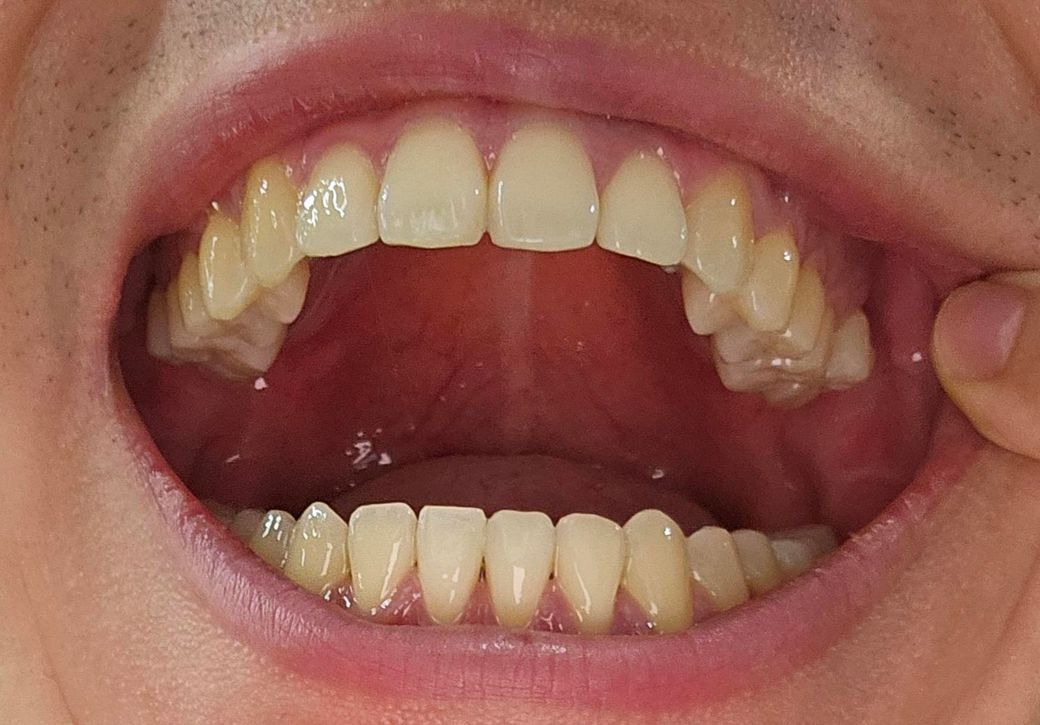

치아 교정한지 1년 반 다되어가는데 동그라미 친 부분 쪽 턱이 아파요.

교합이 맞는지 봐주세요..

안맞아서 턱관절이 아픈걸수도 있을까요?

동그라미 친 부분 반대교합 마무리하였습니다

1. 외견상으론 어금니 1급 교합(정상교합) 상태입니다.

2. 다만, 턱관절에서 모래 갈리는 소리가 난다면 턱관절염을 의심해볼 수 있고, 어금니의 마모 양상을 봤을때 이갈이나 이악물기 습관 등이 존재하는지 의심됩니다.

3. 이러한 습관은 턱관절에 안좋은 영향을 미칠 수 있습니다.